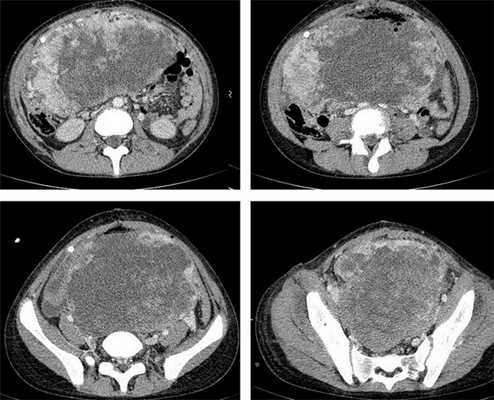

Яичники

Овариальные (расположенные в яичниках, яичниковые) опухоли наиболее часто проявляются болью в животе. При осмотре пальпируется опухоль в малом тазу, часто - в брюшной полости. Также за счет асцита (скопления в брюшной полости жидкости) увеличен живот. Нередко у девочек с таким диагнозом бывает лихорадка.

Самая часто диагностируемая герминогенная опухоль - это дисгерминома. Преимущественно ее обнаруживают во второй декаде жизни. У маленьких девочек встречается редко. Такое заболевания сравнительно быстро распространяется, поражая брюшину и второй яичник. Обычно новообразования односторонние, имеют большие размеры. В связи с этим частое явление - разрыв капсулы новообразования.

Рисунок 3. - тератома яичника а -УЗИ, б — МРТ.

Рисунок 8. КТ органов брюшной полости - на снимках вы можете увидеть опухоль яичника.

Симптомы герминогенных опухолей

Особенности течения заболевания определяются локализацией, размером и степенью злокачественности неоплазии. Типичными симптомами герминогенных опухолей яичника являются боли в животе различной интенсивности в сочетании с нарушениями менструального цикла. У детей последний признак отсутствует, что обуславливает отсутствие настороженности в отношении поражения внутренних половых органов на начальных стадиях заболевания. При прогрессировании герминогенных опухолей к перечисленным симптомам присоединяются увеличение живота и нарушения мочеиспускания. При пальпации на начальных стадиях определяется округлый, умеренно подвижный узел с четкими контурами. В последующем узел увеличивается в размере, возникают увеличение и деформация живота. На поздних стадиях выявляется асцит и нарушения функций различных органов, обусловленные отдаленным метастазированием.

Компьютерная томография органов грудной клетки, брюшной полости, малого таза используются для оценки распространения опухолевого процесса (рис.5).